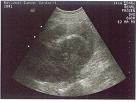

복부초음파검사는 신우 내에 종양이 있는지, 수신증이 있는지, 결석이 신우요관에 발생했는지 등을 감별하는 데 도움을 주는 검사로 간편하고 유용하게 사용됩니다.

[ 복부초음파검사 ]